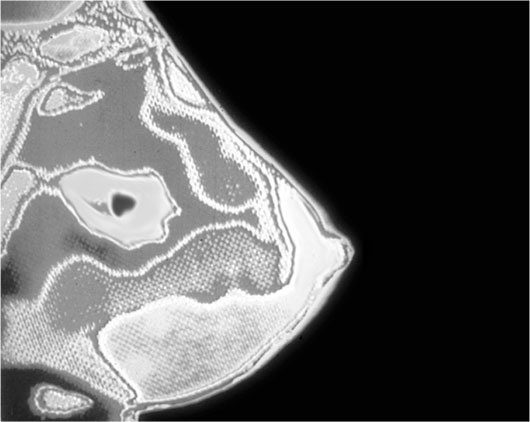

Маммограмма. Обратите внимание, что перед вами не фотография женской груди, а электронное изображение, полученное методом сканирования энергии, излучаемой клетками и тканями этого органа. Особенности в энергетическом спектре позволяют врачам-радиологам отличать здоровые ткани от пораженных заболеванием (темное пятно посередине).

Приведенное на стр. 160 изображение, полученное с помощью энергетического сканирования, свидетельствует о наличии у пациентки рака груди. Больная ткань имеет характерный спектр, отличный от спектра окружающих здоровых тканей. Энергетические образования, проходящие сквозь наше тело, распространяются в виде незримых волн, напоминающих круги на воде. Когда вы бросаете в воду камешек, запасенная им энергия (обусловленная воздействием на него земного тяготения) передается воде. Круги, образуемые вашим камнем, – по существу, это распространяющиеся в воде волны энергии.